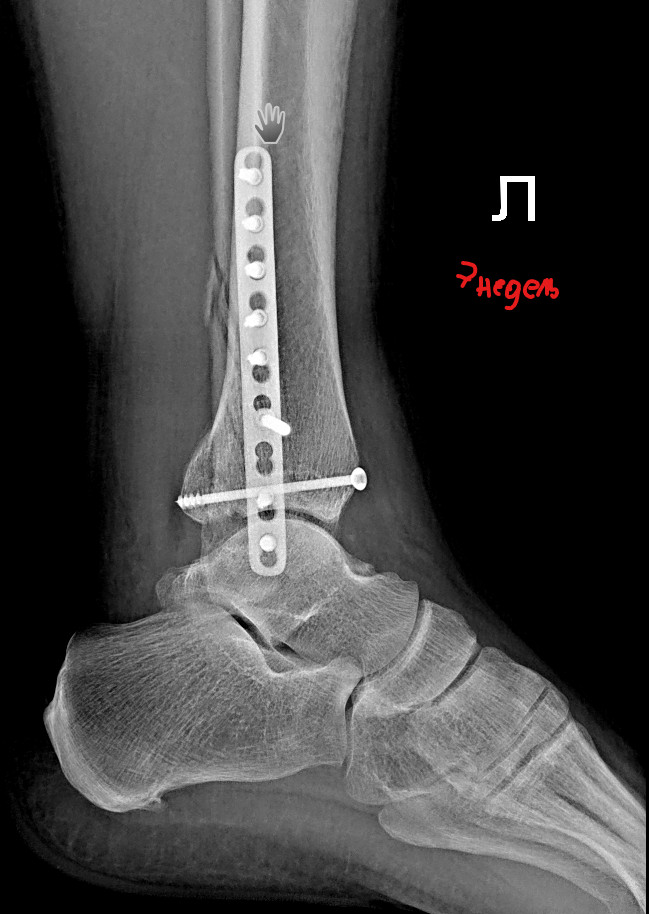

Сегодня, спустя 7 недель, сделал контрольный снимок голеностопа. Прикладываю снимки после оперрации и спустя семь недель. Хочу узнать ваше мнение. Можно начинать лфк, начинать приступать на ногу?

3. Спустя 7 недель https://iimg.su/i/Be028n

4. Спустя 7 недель https://iimg.su/i/8T1HpG

Здравствуйте. По контрольному снимку через 7 недель конструкция стабильна, видно начало консолидации. Можно постепенно начинать щадящую ЛФК (пассивные и активные движения, изометрические упражнения) и опираться на ногу частично в ортезе, полную нагрузку можно после 10-12 недель и повторного контроля. Каждый случай индивидуален, и без очного осмотра точную рекомендацию дать сложно. Поэтому обратитесь к своему ортопеду, для точной оценки.